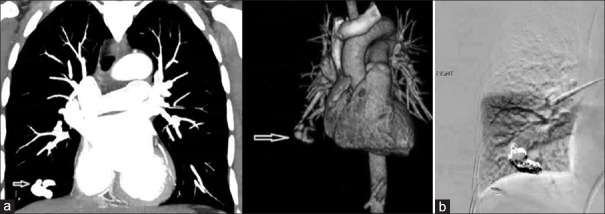

Results: A 47-year-old female presented with acute vertigo and gait imbalance. Magnetic resonance imaging showed AIS in the right cerebellum. CT chest confirmed a PAVM in the right lower lobe. Endovascular coil closure was performed. We identified 102 patients from 96 records. The mean age was 47.4 ± 17 years (67% female). Seventy percent had single AIS and 30% had multiple. The location was anterior circulation in 50%, posterior in 37%, and both in 13%. The most common arterial territory was middle-cerebral (51%), followed by posterior-cerebral (25%). PAVMs were mostly single (78%) and in the lower lobes (66%). Thirty-three had hereditary hemorrhagic telangiectasia (HHT) (33%).

Abstract Image